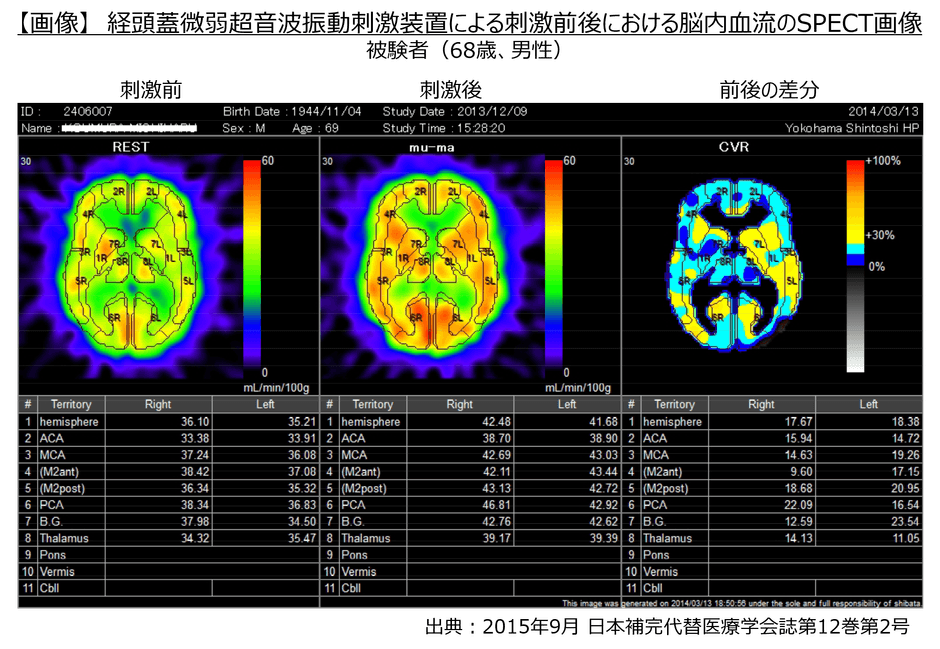

・その結果、イルカが発する30kHzの周波数帯で微弱な振動(2ミリワット/cm2以下)を初老期の健常人に20分間照射することにより脳血流が約15%増加したことが確認されました。

・故小阪憲司先生(世界で初めて脳内・異常蛋白質が原因となるレビー小体型認知症を報告、横浜市立大学名誉教授・精神科医)のご指導のもと、神奈川歯科大学附属病院 認知症・高齢者総合内科 眞鍋雄太教授とともに、中等度のDLB患者に対して特定臨床研究を実施した結果、特に運動機能障害の顕著な改善が認められました。(下記画像参照)